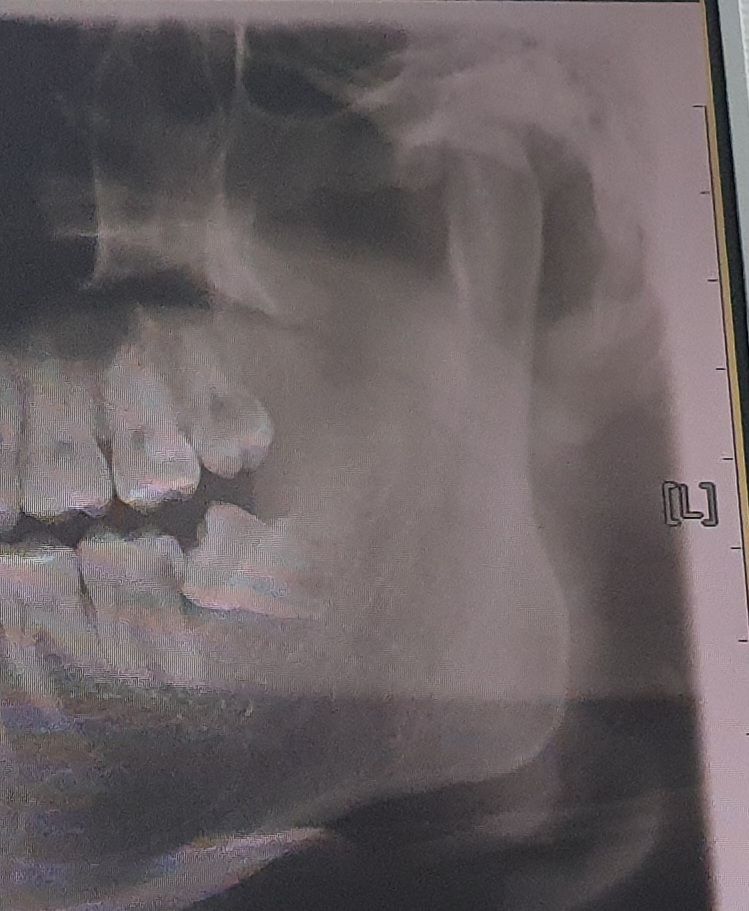

어금니 신경치료가 필요한데 혹시 사랑니 구멍이 다메워져야 가능한건가요?

사랑니는 현재 발치한 상태이고 제2대구치 신경치료가 필요한 상황입니다. 싱경치료와 크라운을 진행하려면 구멍이 다 메워져야한다는데 맞나요?

치근단 엑스레이 사진이 있다면 좀 더 도움되는 답변을 드릴 수 있을 것 같습니다. 아마도 기다려야 하는 이유는 충치가 옆면까지 있어서 그쪽 충치를 제거하고 먼저 떼운 뒤 (레진월 형성) 신경치료를 시작하는데 이때 떼우려면 발치 부위 잇몸이 어느정도 아물어 출혈, 삼출물이 나오지 않는 상태여야 하기 때문입니다.